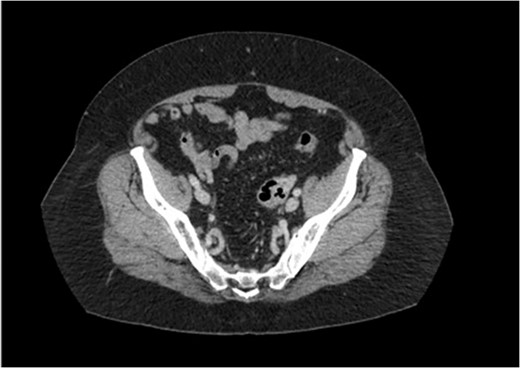

A transvaginal ultrasound, obtained by the patient’s gynecologist, showed a linear hyperechoic structure within the fundal portion of the endometrial canal. The suspicion was that of a retained intrauterine device. In addition, there was a right-sided avascular complex cyst measuring 2.5 × 2.2 × 1.8 cm3. A CT scan of the pelvis was then obtained. The CT scan, highlighted in Figs 1 and 2, revealed multiple foci of gas within the left ovary and fistulization of the adjacent sigmoid colon with questionable air in the fallopian tube.